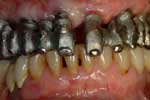

Protesi fissa completamente ancorato ad impianti in arcata superiori e riabilitazione parziale su impianti nei settori posteriori ed anteriori

CASO INIZIALE